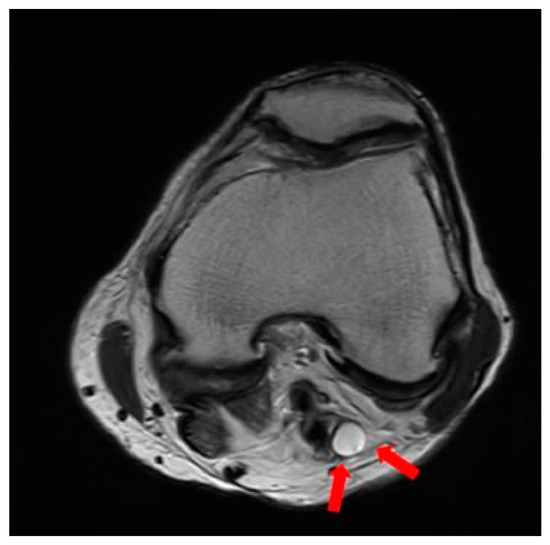

2.1. Preoperative Evaluation